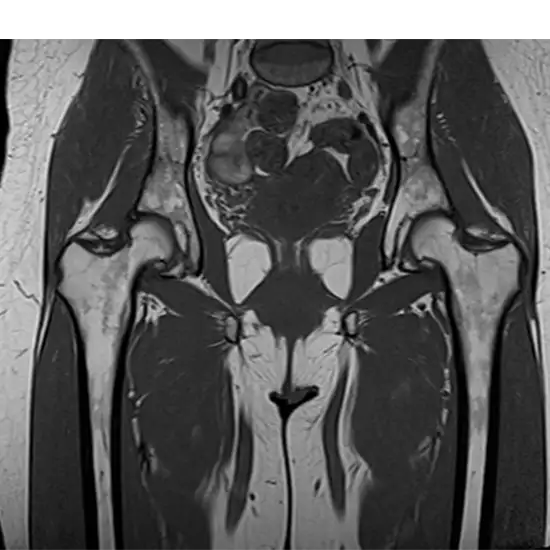

An MRI of the left hip joint is used to see the hip joint, the bones that make up the joint, and the soft tissues, including tendons, ligaments, muscles, and blood vessels surrounding it.

The physician orders this test to diagnose any fracture of the bones that comprise the hip joint, as well as any suspected dislocation of the hip and arthritis of this joint.